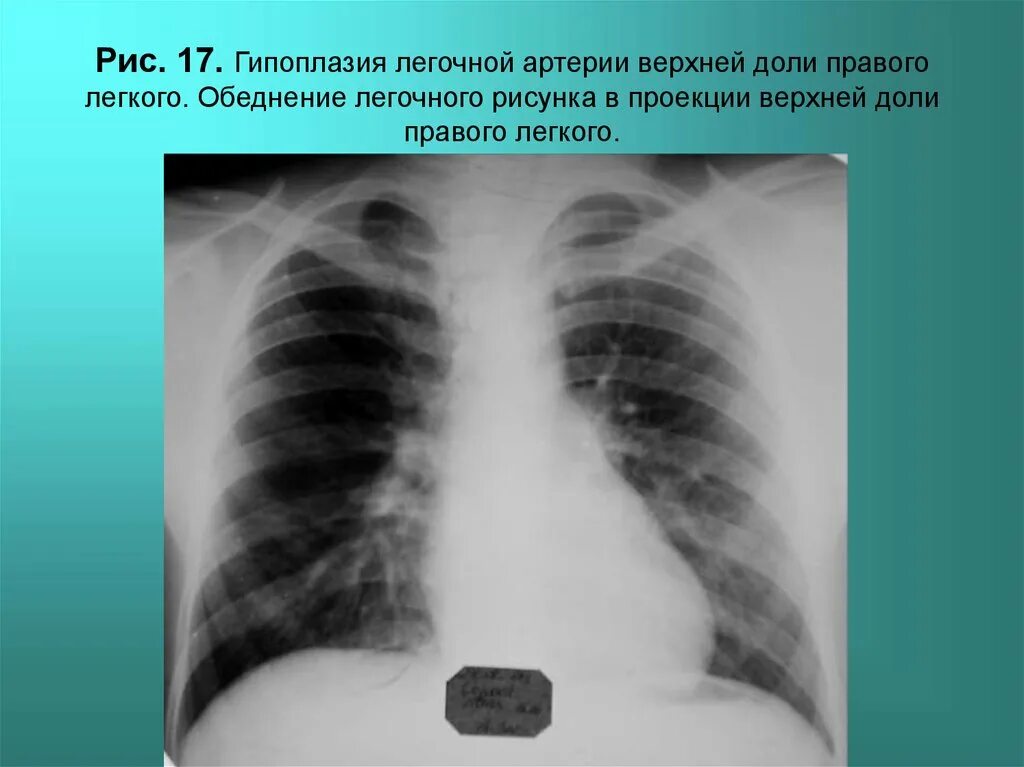

Гипоплазия 12 пары ребер